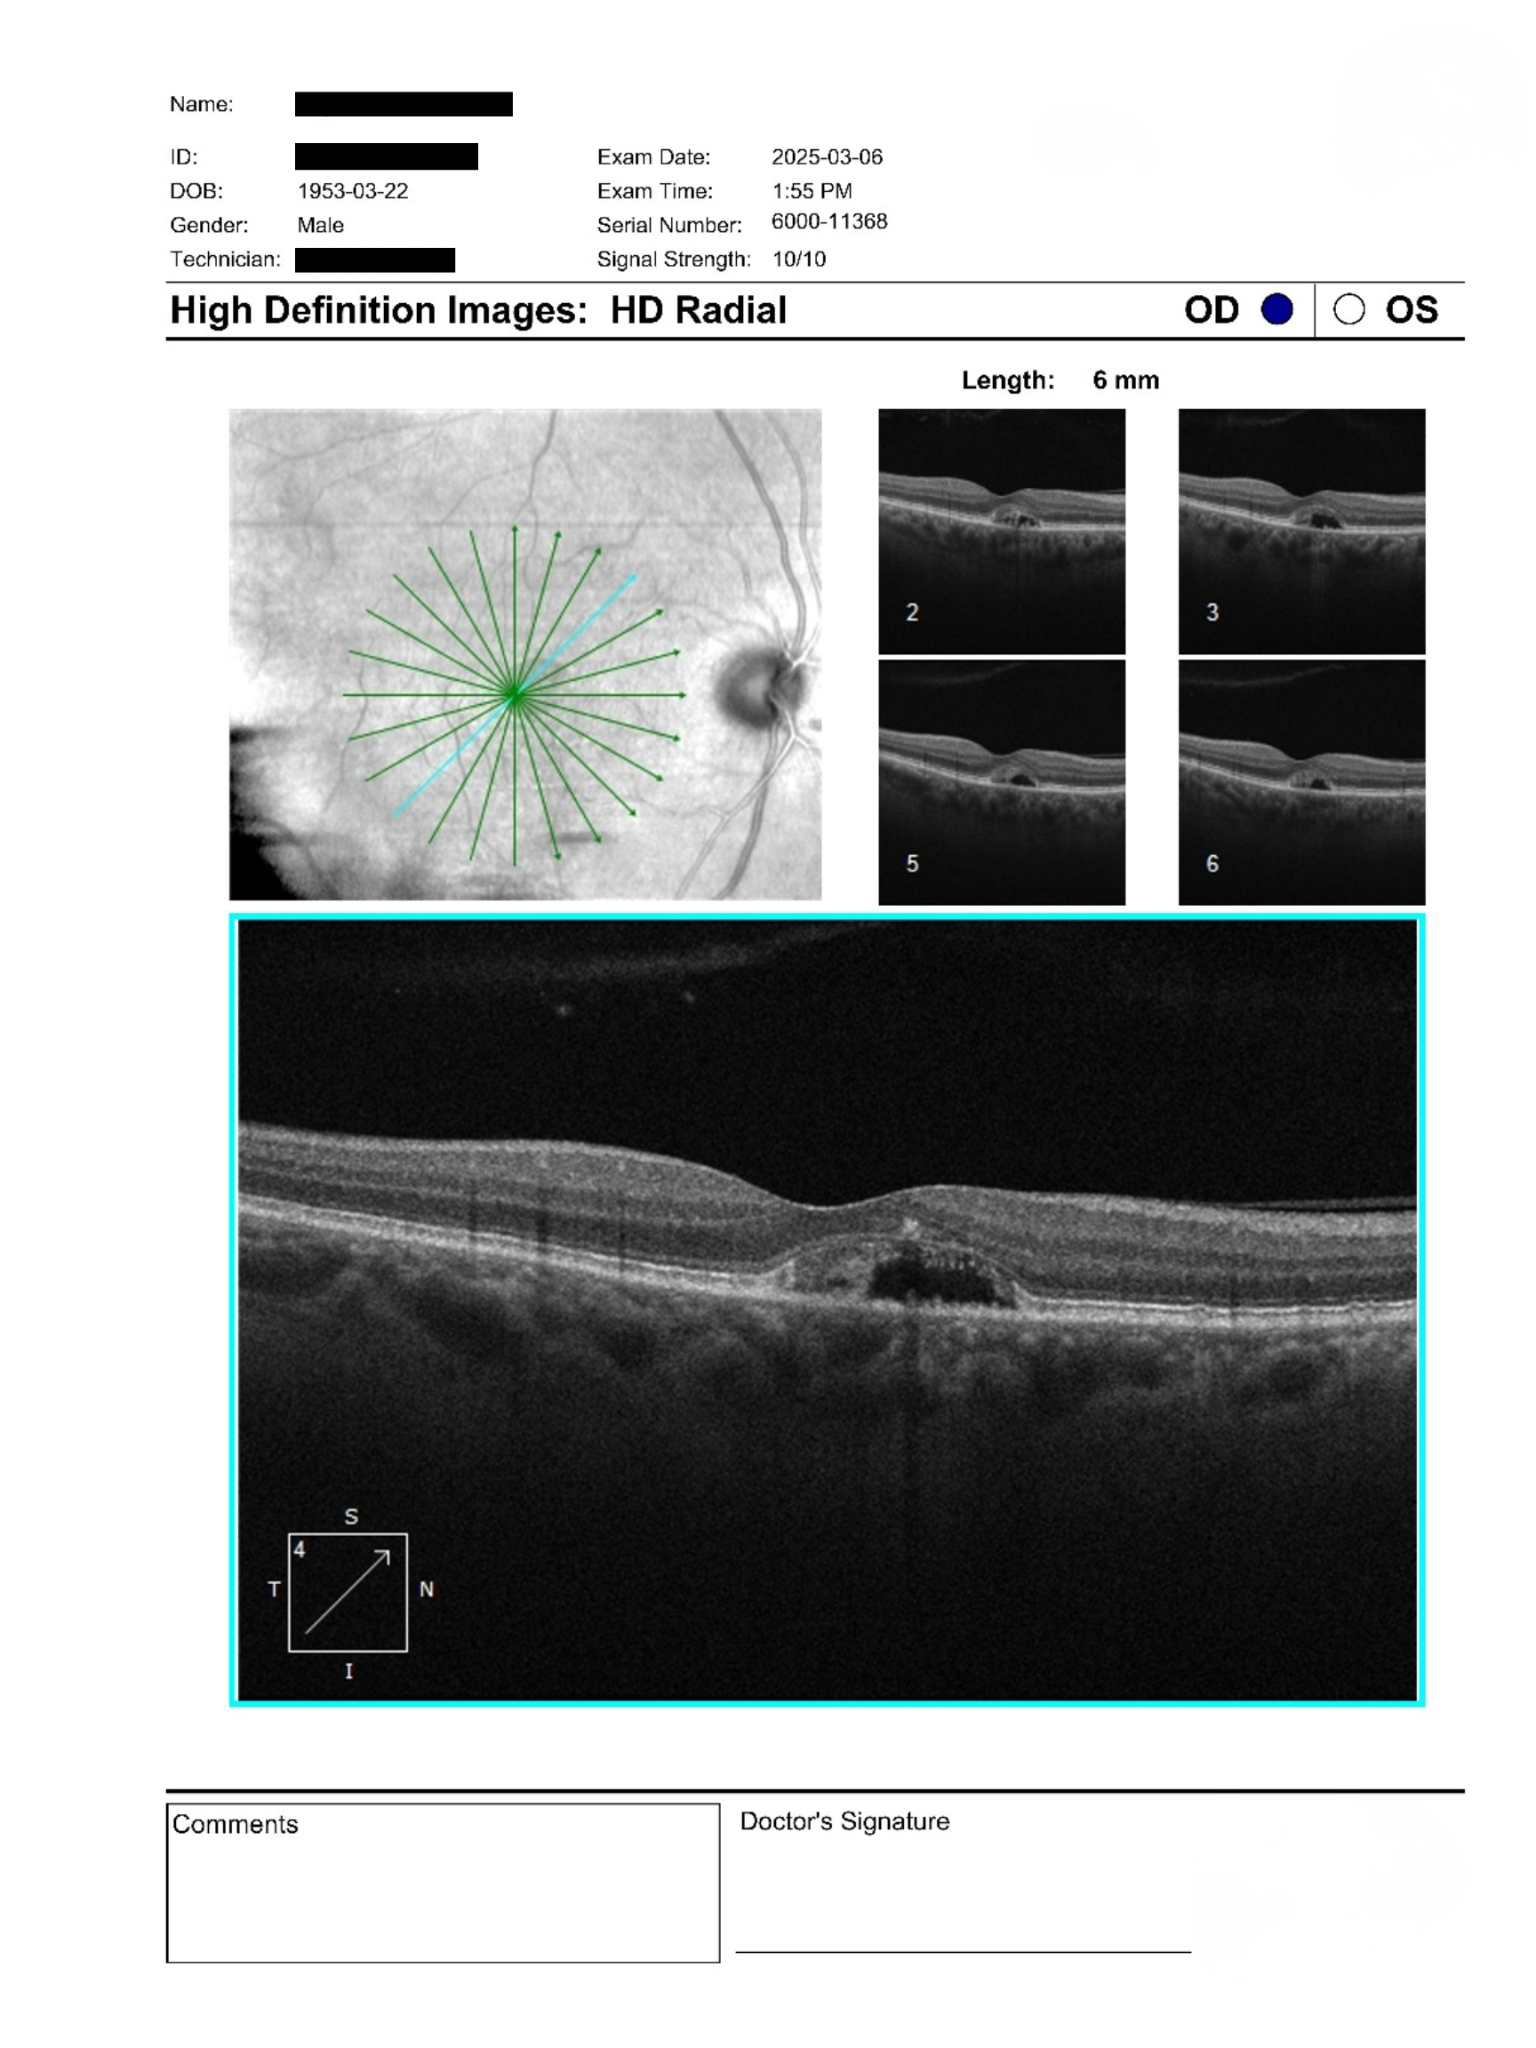

73-year-old with blurred vision and macular elevation on OCT showing central changes and subretinal features requiring further assessment.

A 73-year-old male was referred for reduced near vision and suspected macular changes. BCVA was 20/50 OU and IOPs were 20 and 21 mmHg. Anterior segment exam showed mild nuclear sclerosis cataracts. Posterior segment exam revealed subtle macular pallor with OCT demonstrating central elevation and cystic spaces suggestive of subretinal pathology. The patient denied acute visual changes.

The imaging demonstrates bilateral vitelliform-like deposits with signs of partial reabsorption and associated basal laminar changes. There is no clear evidence of active exudation, though subtle subretinal alterations warrant caution. The likelihood of neovascular activity appears low, but cannot be definitively excluded based on current imaging alone.

Referral for advanced imaging such as IVFA and OCTA is recommended to further evaluate for occult neovascularization. In the interim, conservative management with nutritional supplementation, UV protection, and home monitoring using an Amsler grid is appropriate. Ongoing follow-up is essential to detect progression.

Vitelliform lesions are characterized by subretinal deposits of lipofuscin-like material, often associated with retinal pigment epithelium dysfunction. These findings can overlap with other macular conditions and may evolve over time, including partial resorption stages. Multimodal imaging is key for accurate characterization and differentiation.